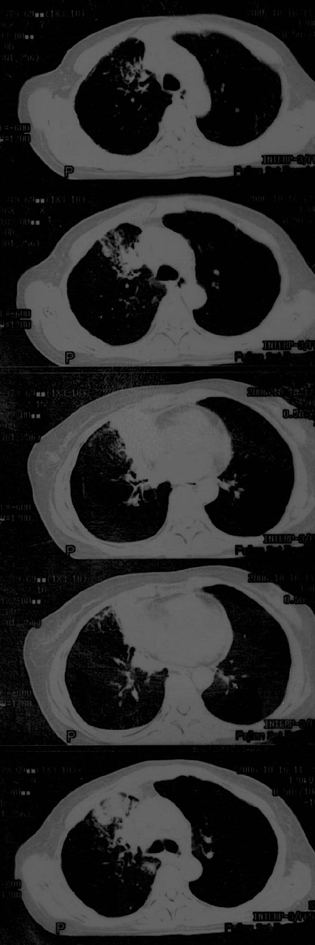

母亲67岁,咳嗽,无血痰。发病已两月余,抗生素无效

传上图片看不清,可是给我的感觉是恶性的,虽然还需跟肺结核相鉴别.

片子不清,右肺下叶像个结核球,右肺上叶需要做个支气管镜检查,除外中心型肺癌。个人意见,其他老师们再看看。